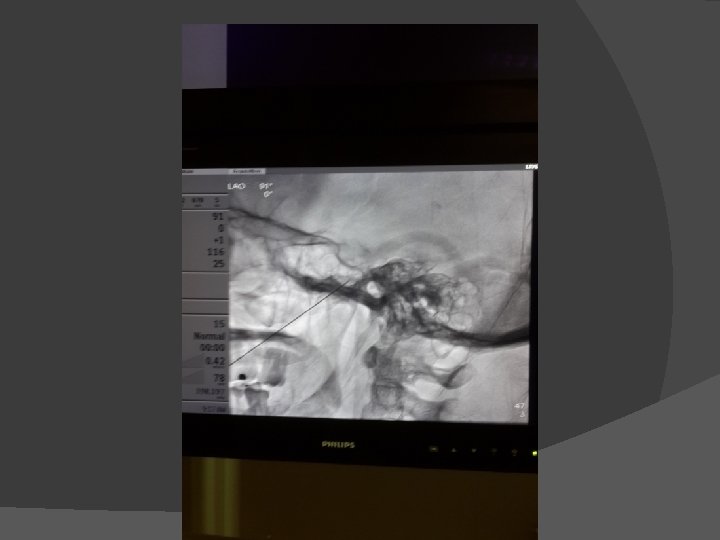

Trigeminal Neuralgia � Gasserian ganglian block/ neurolysis

� Kasus 1 Laki-laki, 60 th, mengeluh nyeri selama 10 tahun di wajah sisi kanan, hilang timbul seperti tersengat listrik. DM (+), HT(+), mendapat terapi carbamazepin dan pregabalin namun nyeri berkurang hanya sedikit. TRIGEMINAL GANGLION RADIOFREQUENCY